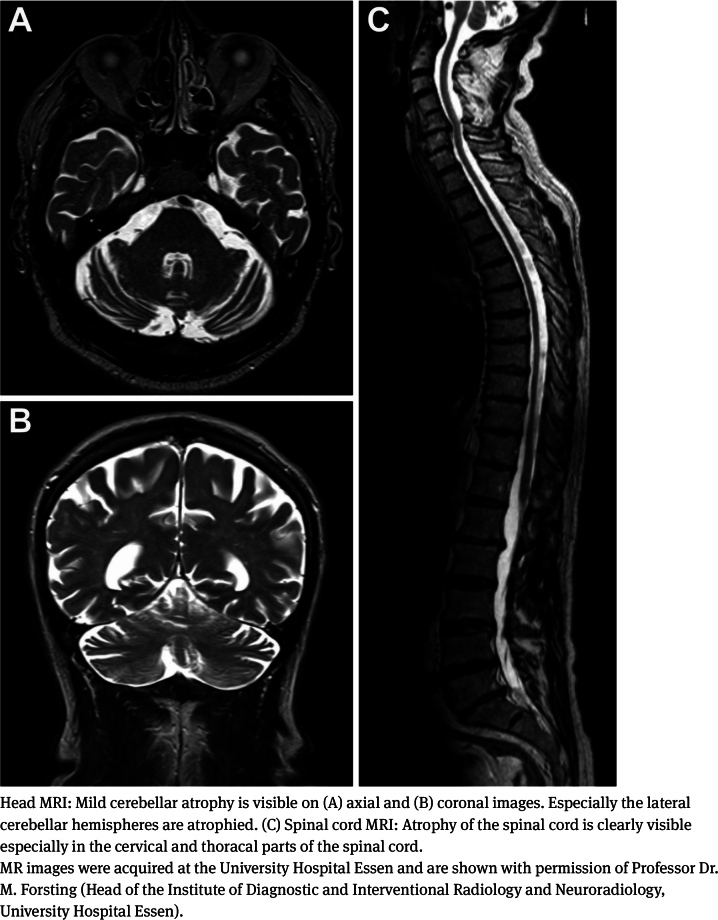

The cerebellar ataxia, neuropathy and vestibular areflexia syndrome (CANVAS) is a late-onset and recessively inherited ataxia. For many years, CANVAS has been diagnosed based on the clinical phenotype. Only recently, a large biallelic pentanucleotide repeat expansion in the replication factor C subunit 1 (RFC1) gene has been identified as the underlying genetic cause for the large majority of CANVAS cases. Subsequently, other phenotypes such as ataxia with chronic cough, incomplete CANVAS and MSA-C-like phenotypes have been associated with biallelic RFC1 repeat expansions. Because of this heterogeneity it has been suggested to change the name of the disease to "RFC1 disease". Chronic cough is characteristic and can precede neurological symptoms by years or decades. In the neurological examination signs of cerebellar, sensory, and vestibular ataxia are frequently observed. Nerve conduction studies usually show absent or markedly reduced sensory nerve action potentials. On brain MRI cerebellar degeneration and spinal cord alterations are common. In later disease stages more widespread neurodegeneration with additional involvement of the brainstem and basal ganglia is possible. As yet, the exact incidence of RFC1-associated neurological diseases remains uncertain although first studies suggest that RFC1-related ataxia is common. Moreover, the pathophysiological mechanisms caused by the large biallelic pentanucleotide repeat expansions in RFC1 remain elusive. Future molecular and genetic research as well as natural history studies are highly desirable to pave the way towards personalized treatment approaches.